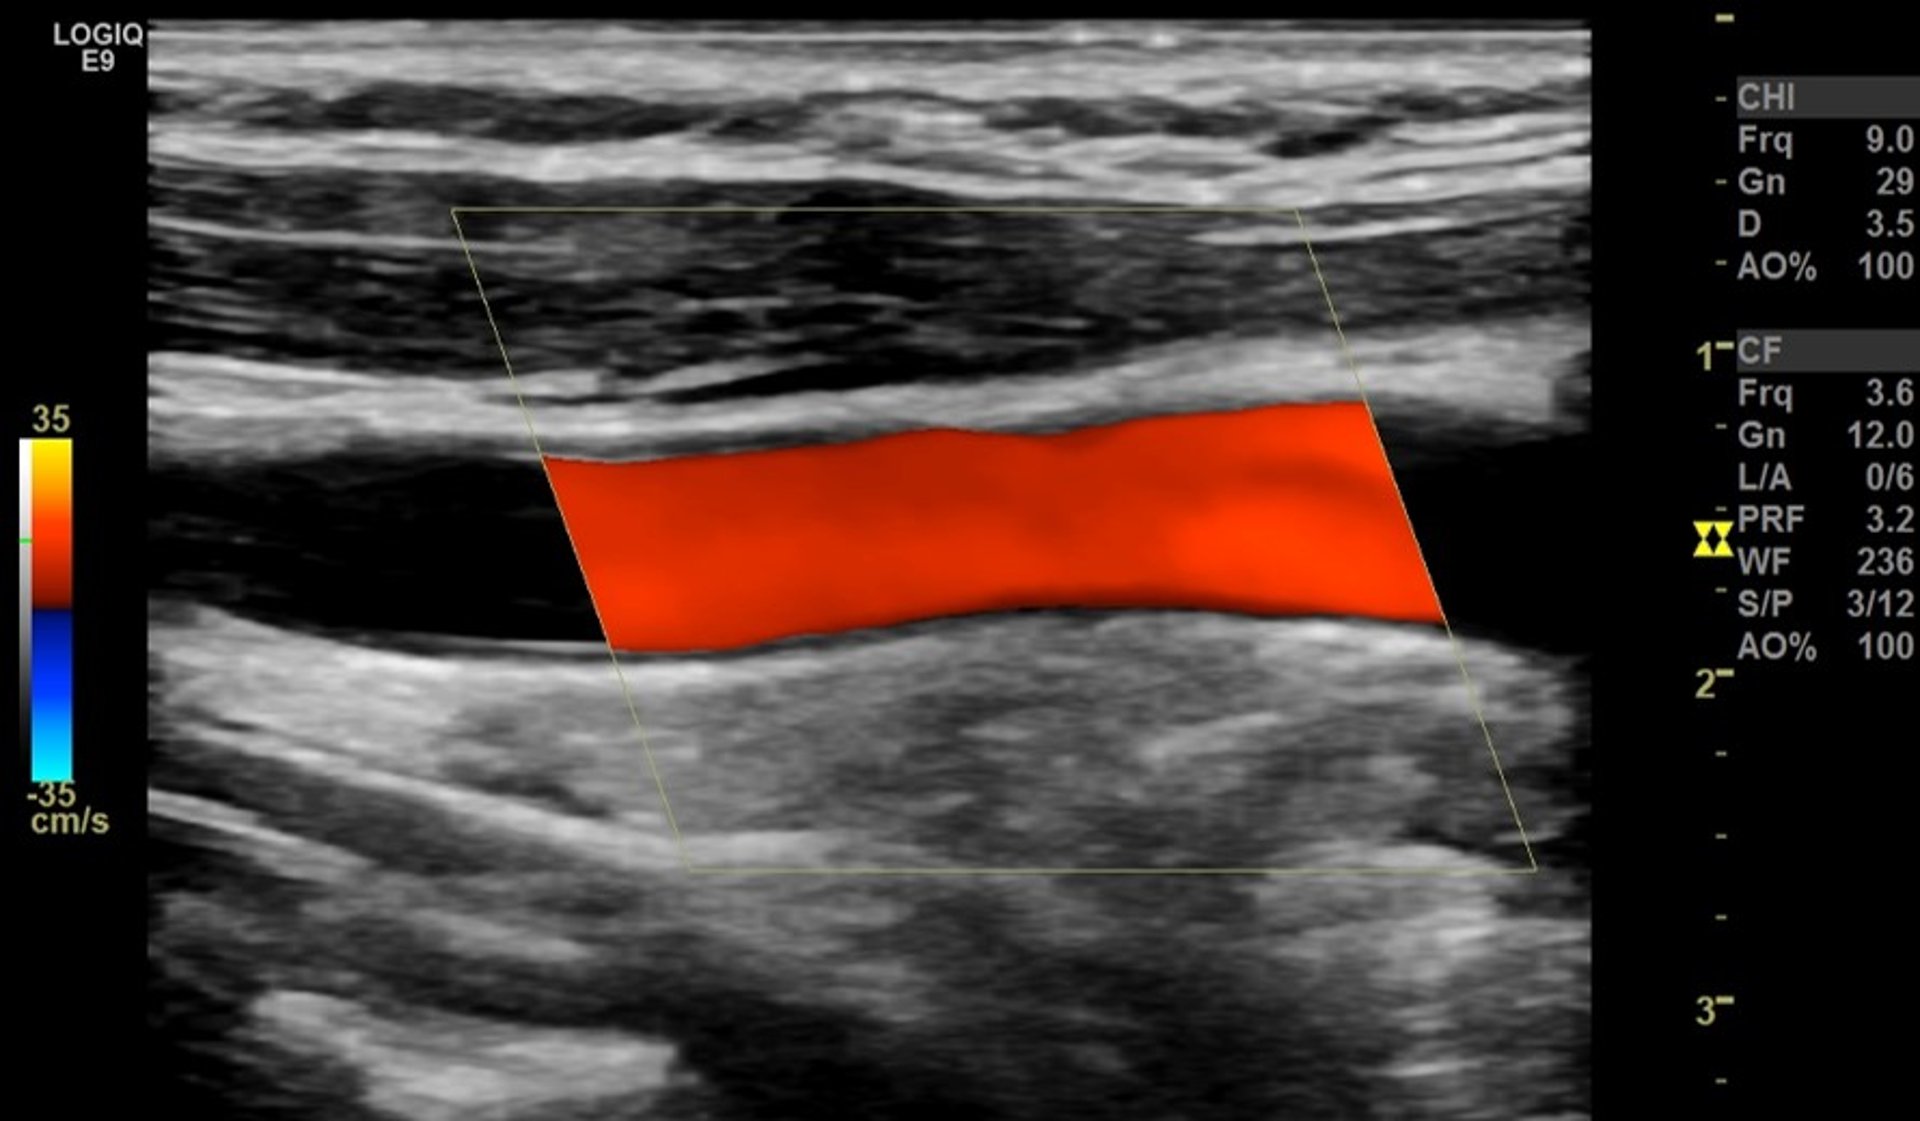

Échographie Doppler couleur de l’artère carotide

La bande rouge représente un flux sanguin normal et non obstrué dans une grosse artère du cou (artère carotide commune), visualisée sur le côté.

Image fournie par le Dr Mustafa Mafraji